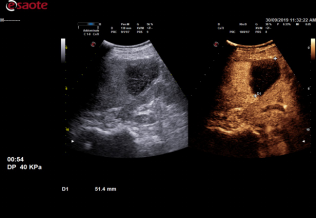

• 编码脉冲激励成像(CPI):

不能频率的超声在成像的分辨率和深度上有所不同,高频超声增加了分辨率却降 低了检测深度。百胜 X7 VET 超声仪根据不同检查深度,均衡发射脉冲频率,实现编 码群发射成像, 使组织谐波成像和造影多波段接收效率大大提高, 提高远场穿透力, 进而能够提高肥胖或大型动物的图像质量。

CPI OFF

CPI ON